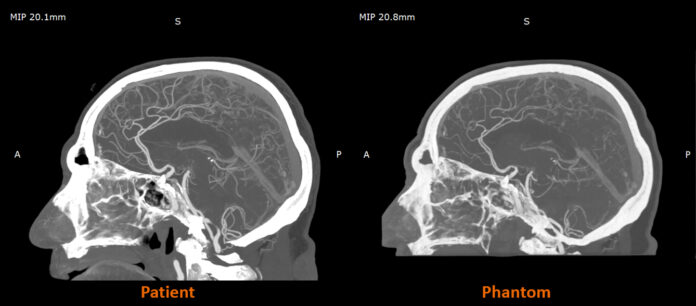

Stratasys said the material is already showing impact in early deployments. In the United Kingdom, projects with CPI and Beaumont Hospital have used radio-realistic cerebral angiography phantoms to improve training environments and enhance control and repeatability in imaging research. By pairing Digital Anatomy 3D printing technology with the new radiopaque material, Stratasys and Siemens Healthineers are developing anatomically detailed, radio-accurate models that can serve as scalable and ethical alternatives to cadavers for imaging education, protocol development and algorithm testing.

RadioMatrix is the first 3D printing material engineered to offer precise control over radiopacity, enabling production of patient-specific anatomical models with predictable visibility on CT and other X-ray imaging systems. Stratasys developed the material to support more advanced medical imaging workflows, and its performance has been validated in studies conducted with Siemens Healthineers. According to the company, the collaboration demonstrated that RadioMatrix phantoms can replicate human tissue with deviations as low as single Hounsfield units in key structures such as grey matter and vasculature.